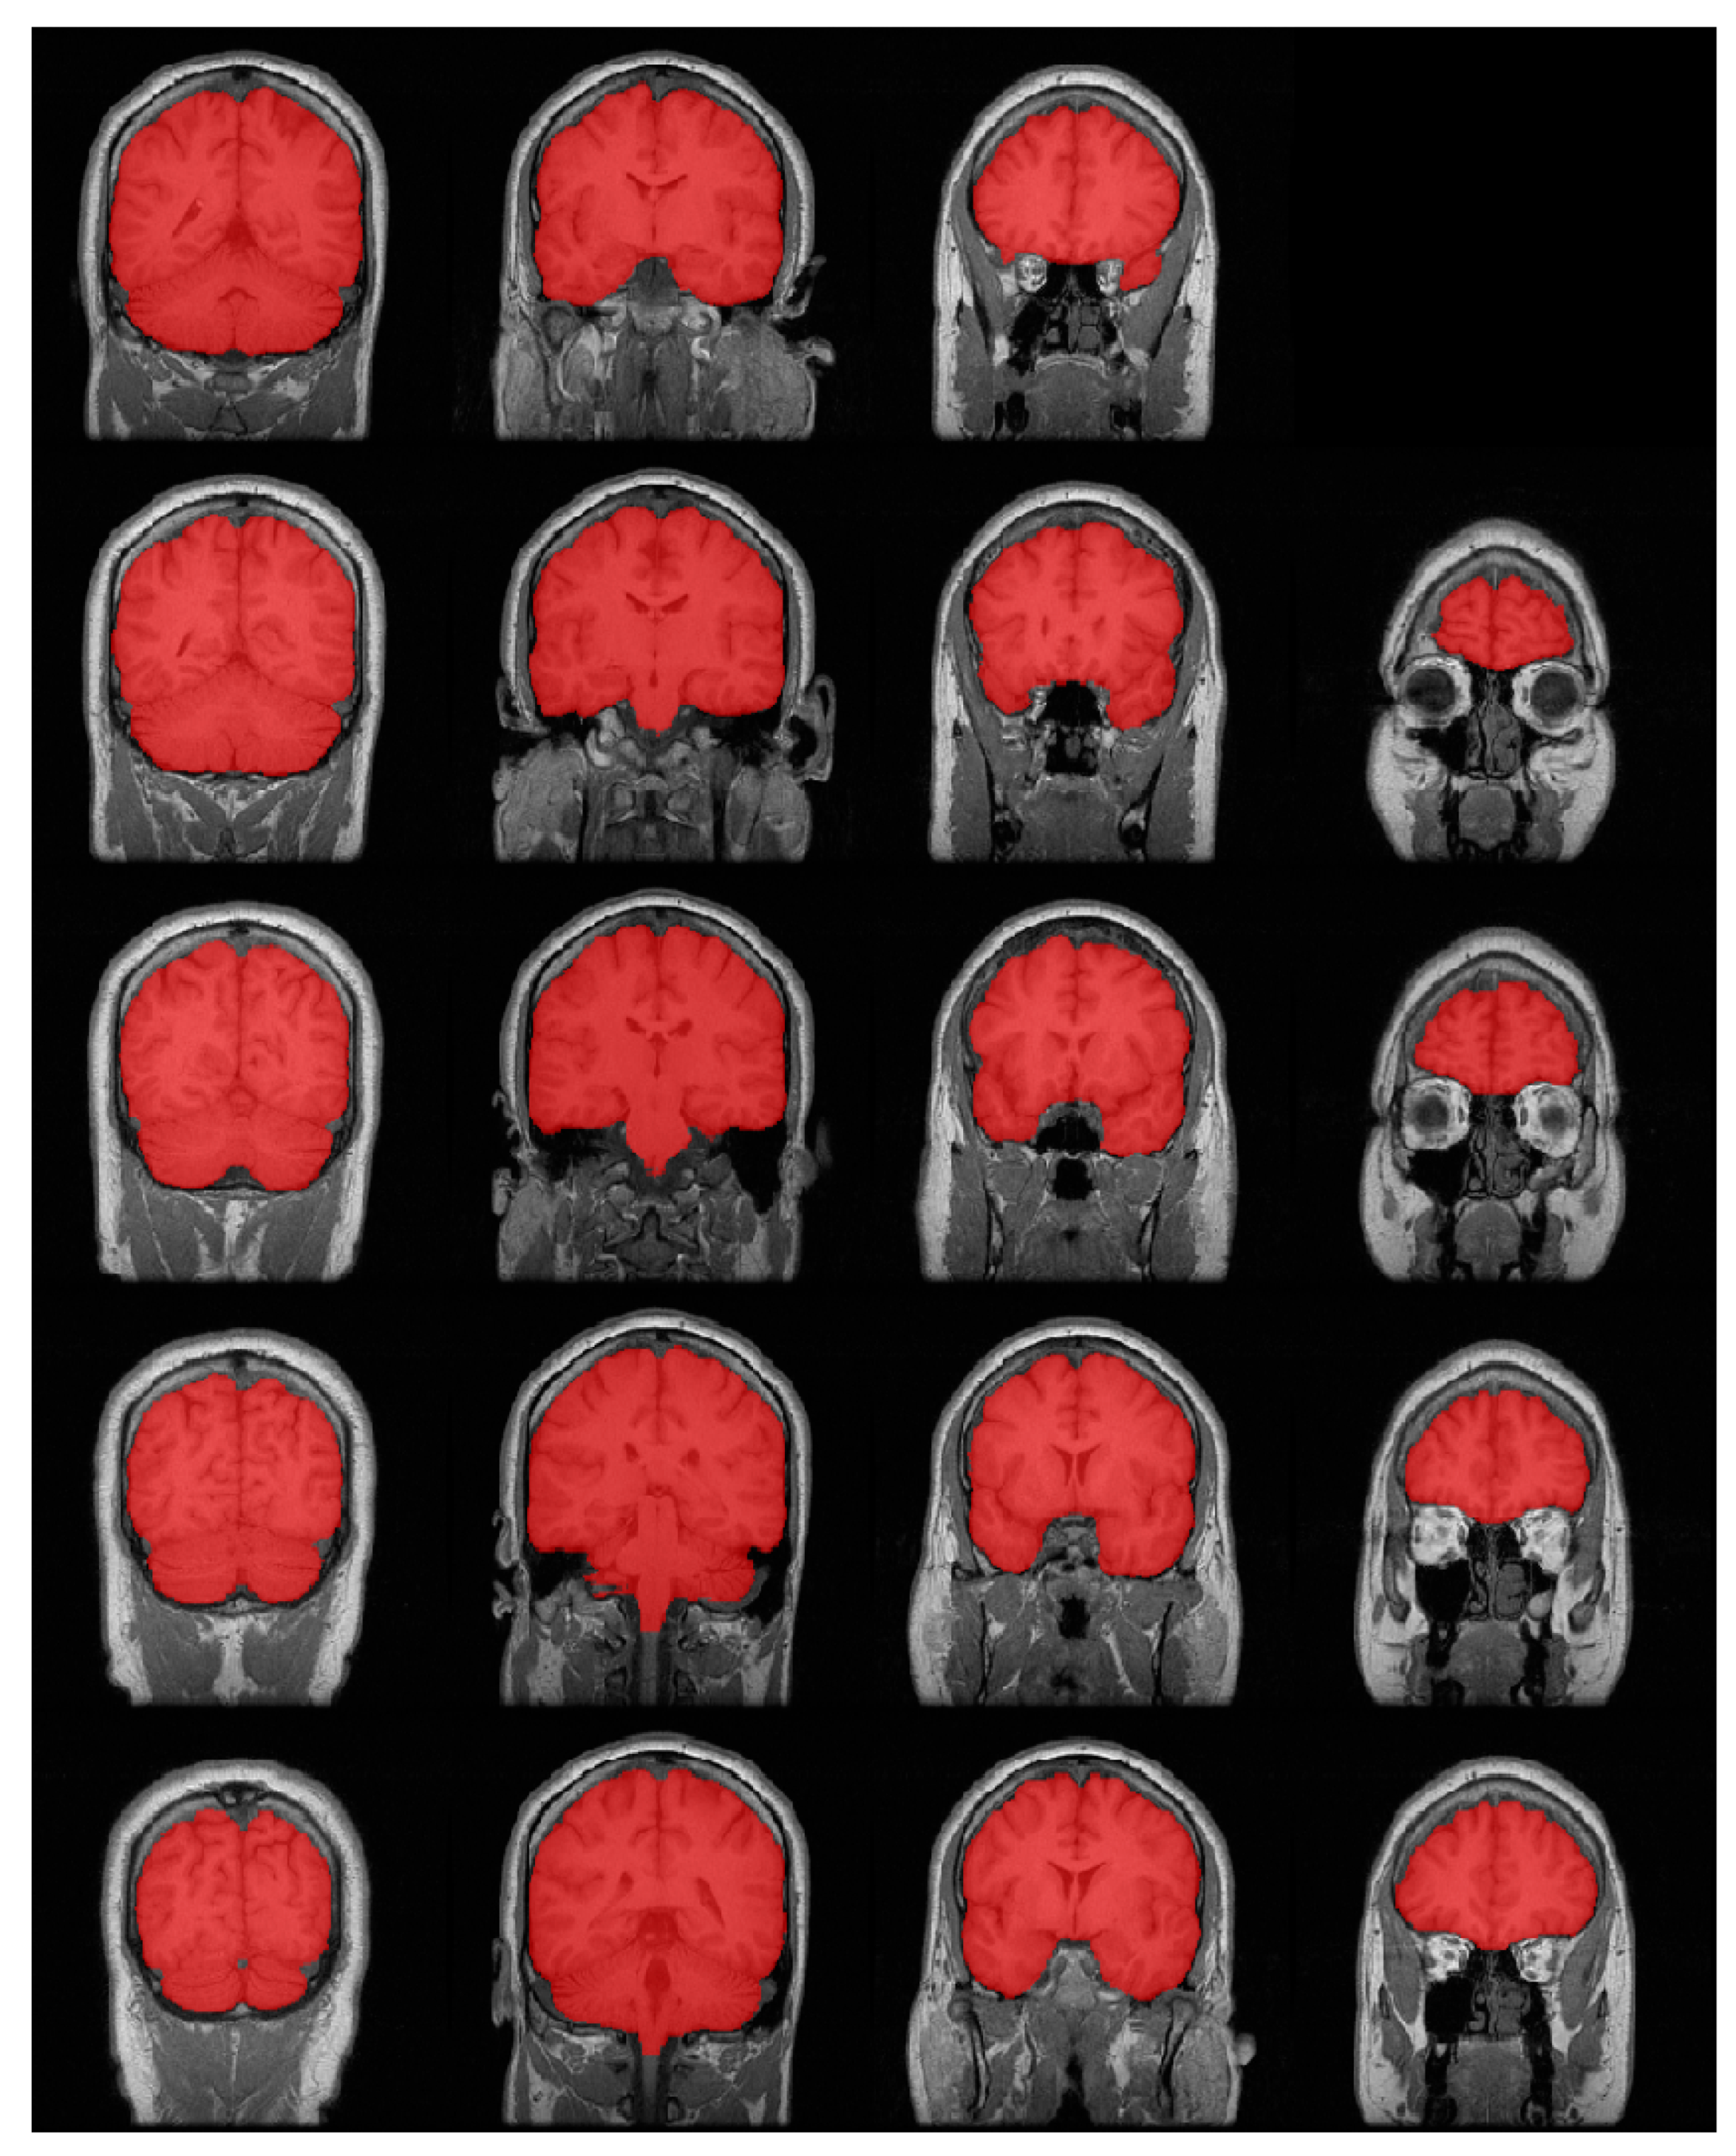

:1. Introduction

2.1. Network Architecture

2.2. Full Image Information Mining with a K-Means Cluster Preprocessing

2.3. Hybrid-U-Net Framework

2.4. Dimensionality Reduction U-Net for 3D MRI Data

3.2. Results